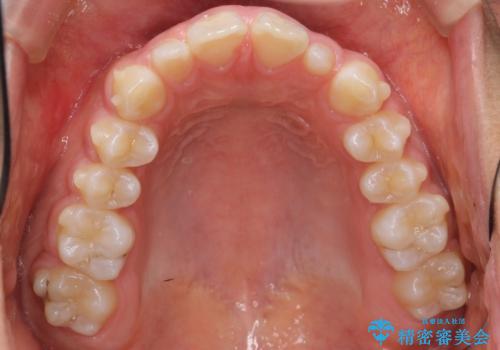

前歯のすきま 矯正治療とセラミックで小さな歯を形良く

- 前歯のすきまを気にして来院。

左上の2番が生まれつき小さく、スペースが余っていました。

右上の2番もやや小さめでしたが、相談の上、左上2番のみセラミックで形を整えることとしました。

そのほかの隙間はマウスピース矯正で閉じることにしました。

当初はワイヤー矯正を希望されていましたが、右上7番の頬側に咬頭があり、ブラケットを貼ることが難しいため、こちらからマウスピース矯正をお勧めしました。